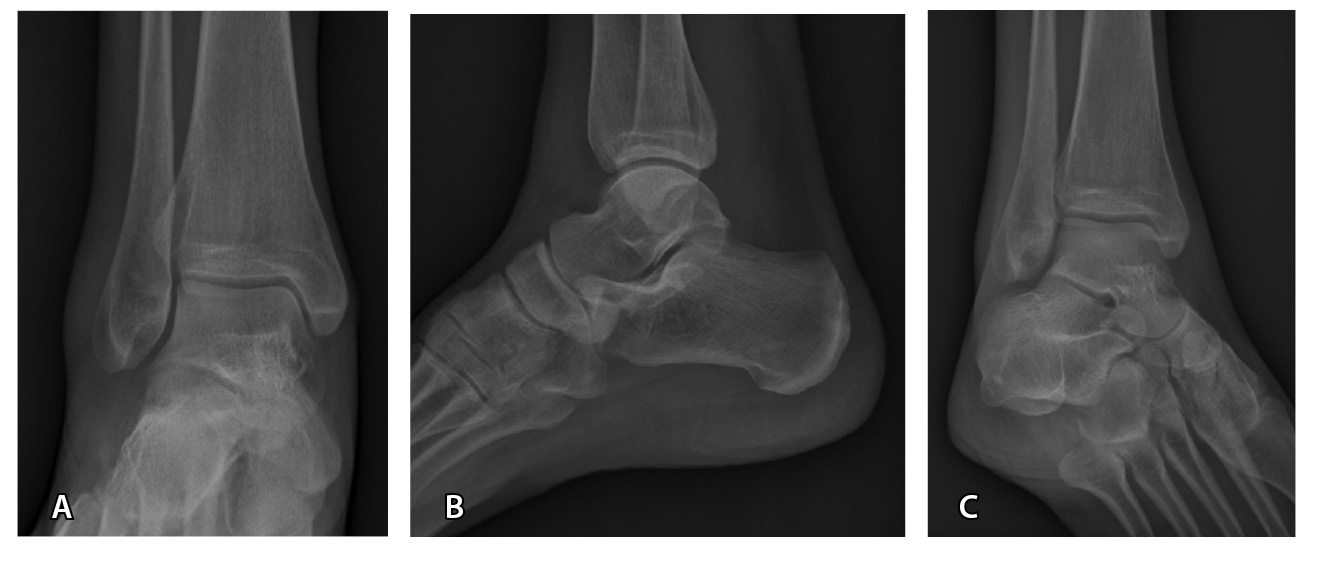

Стандартизированный подход к визуализации помогает снизить количество диагностических ошибок [34]. Стандартный протокол рентгенографии голеностопного сустава представлен в табл. 1 и на рис. 1.

Рис. 1. Стандартный протокол рентгенографии голеностопного сустава без осевой нагрузки: А – прямая проекция; Б – боковая проекция; В – прямая проекция с внутренней ротацией стопы на 20°. Костно-травматические изменения не определяются, параартикулярные мягкие ткани не изменены